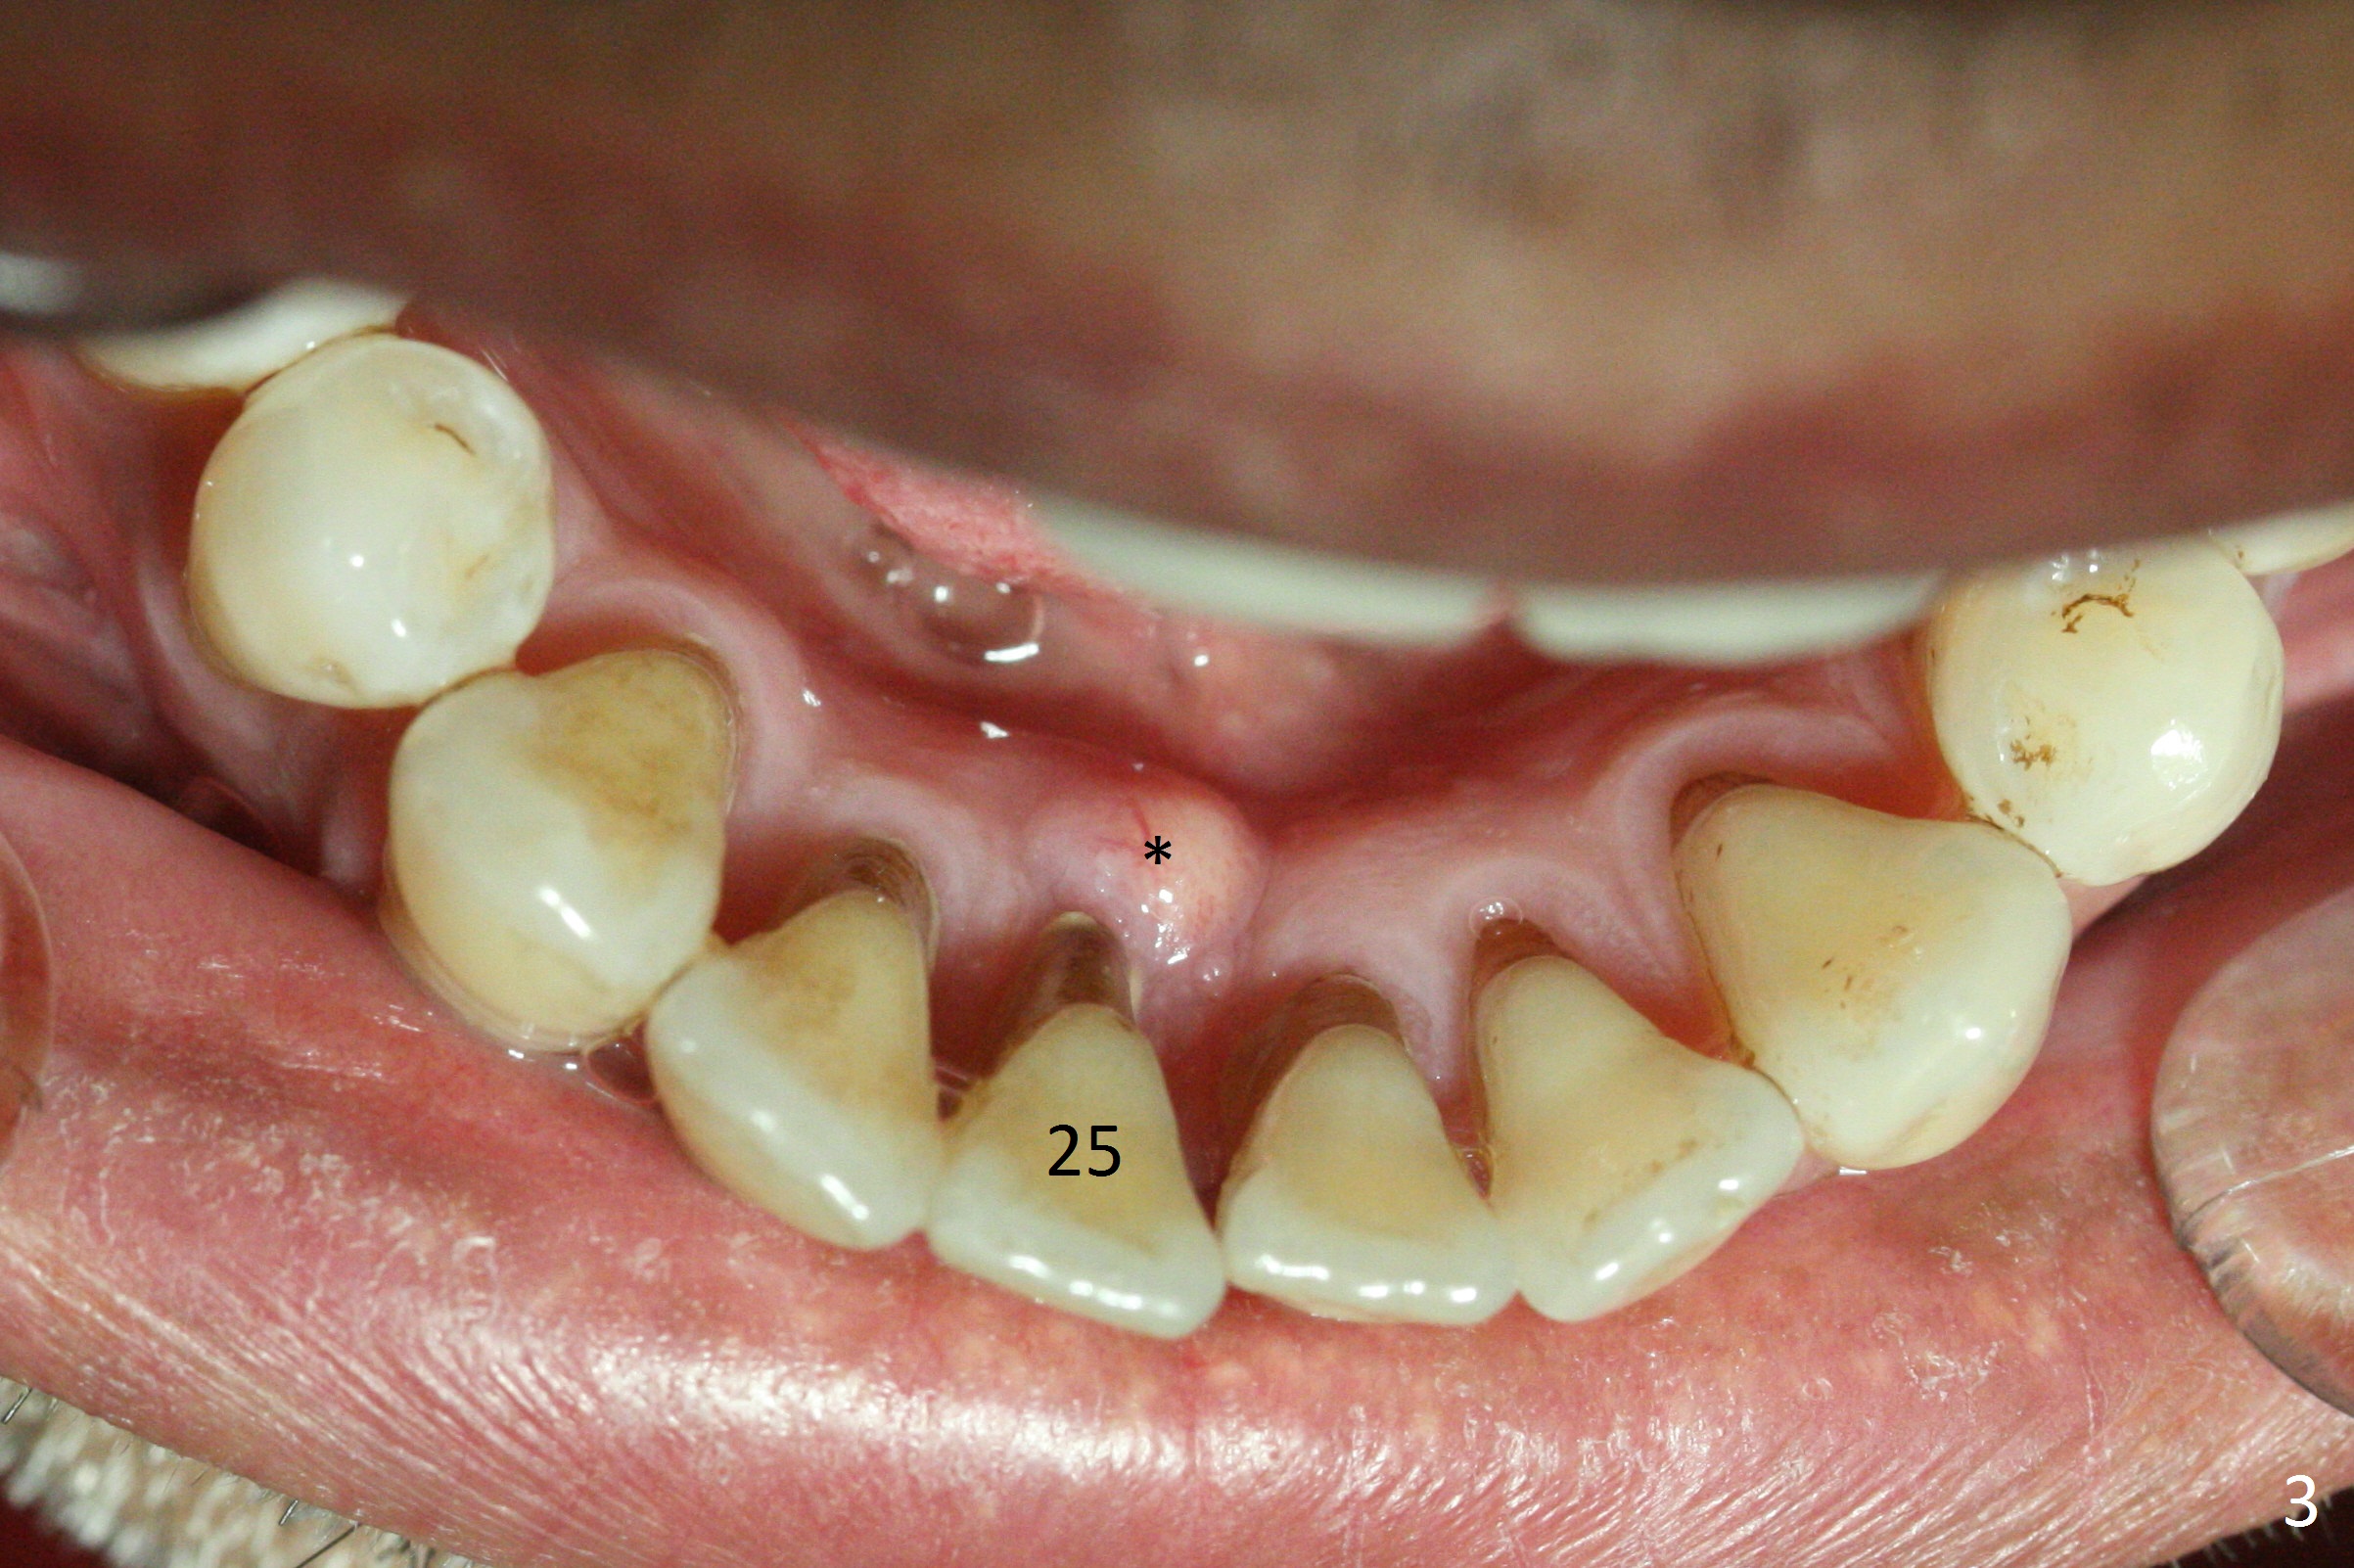

A 48-year-old man is determined to have implants for mobile teeth #14 and 25 (Fig.1).  He is not pleased with the upper anterior FPD because of difficulty in cleaning.  In addition to severe gingival recession (Fig.2), there is an abscess lingual to the tooth #25 (Fig.3).   The latter should be associated with lingual plate defect.  Osteotomy should be initiated in the center of the socket, in contrast to usual lingual starting point.  A 3x16(4) mm 1-piece implant is to be placed unless the socket is small buccolingually or mesiodistally.  Take PA immediately after his arrival for surgery to determine the mesiodistal width and the gingival thickness.  The 2nd parameter will decide what parameter of the implant?

This patient is pleased to learn that an immediate provisional will be fabricated.  The anterior open bite (Fig.2) will make the job easier.